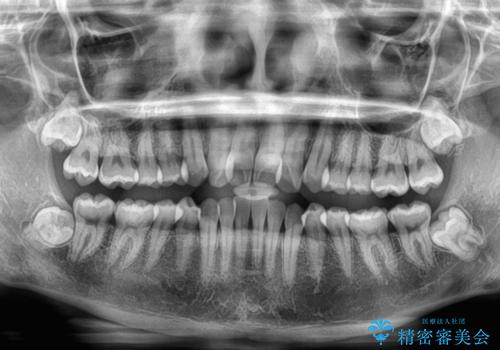

- 上顎前歯のクロスバイトを気にして来院された患者様です。

- 症状により、抜歯が必要な場合があります